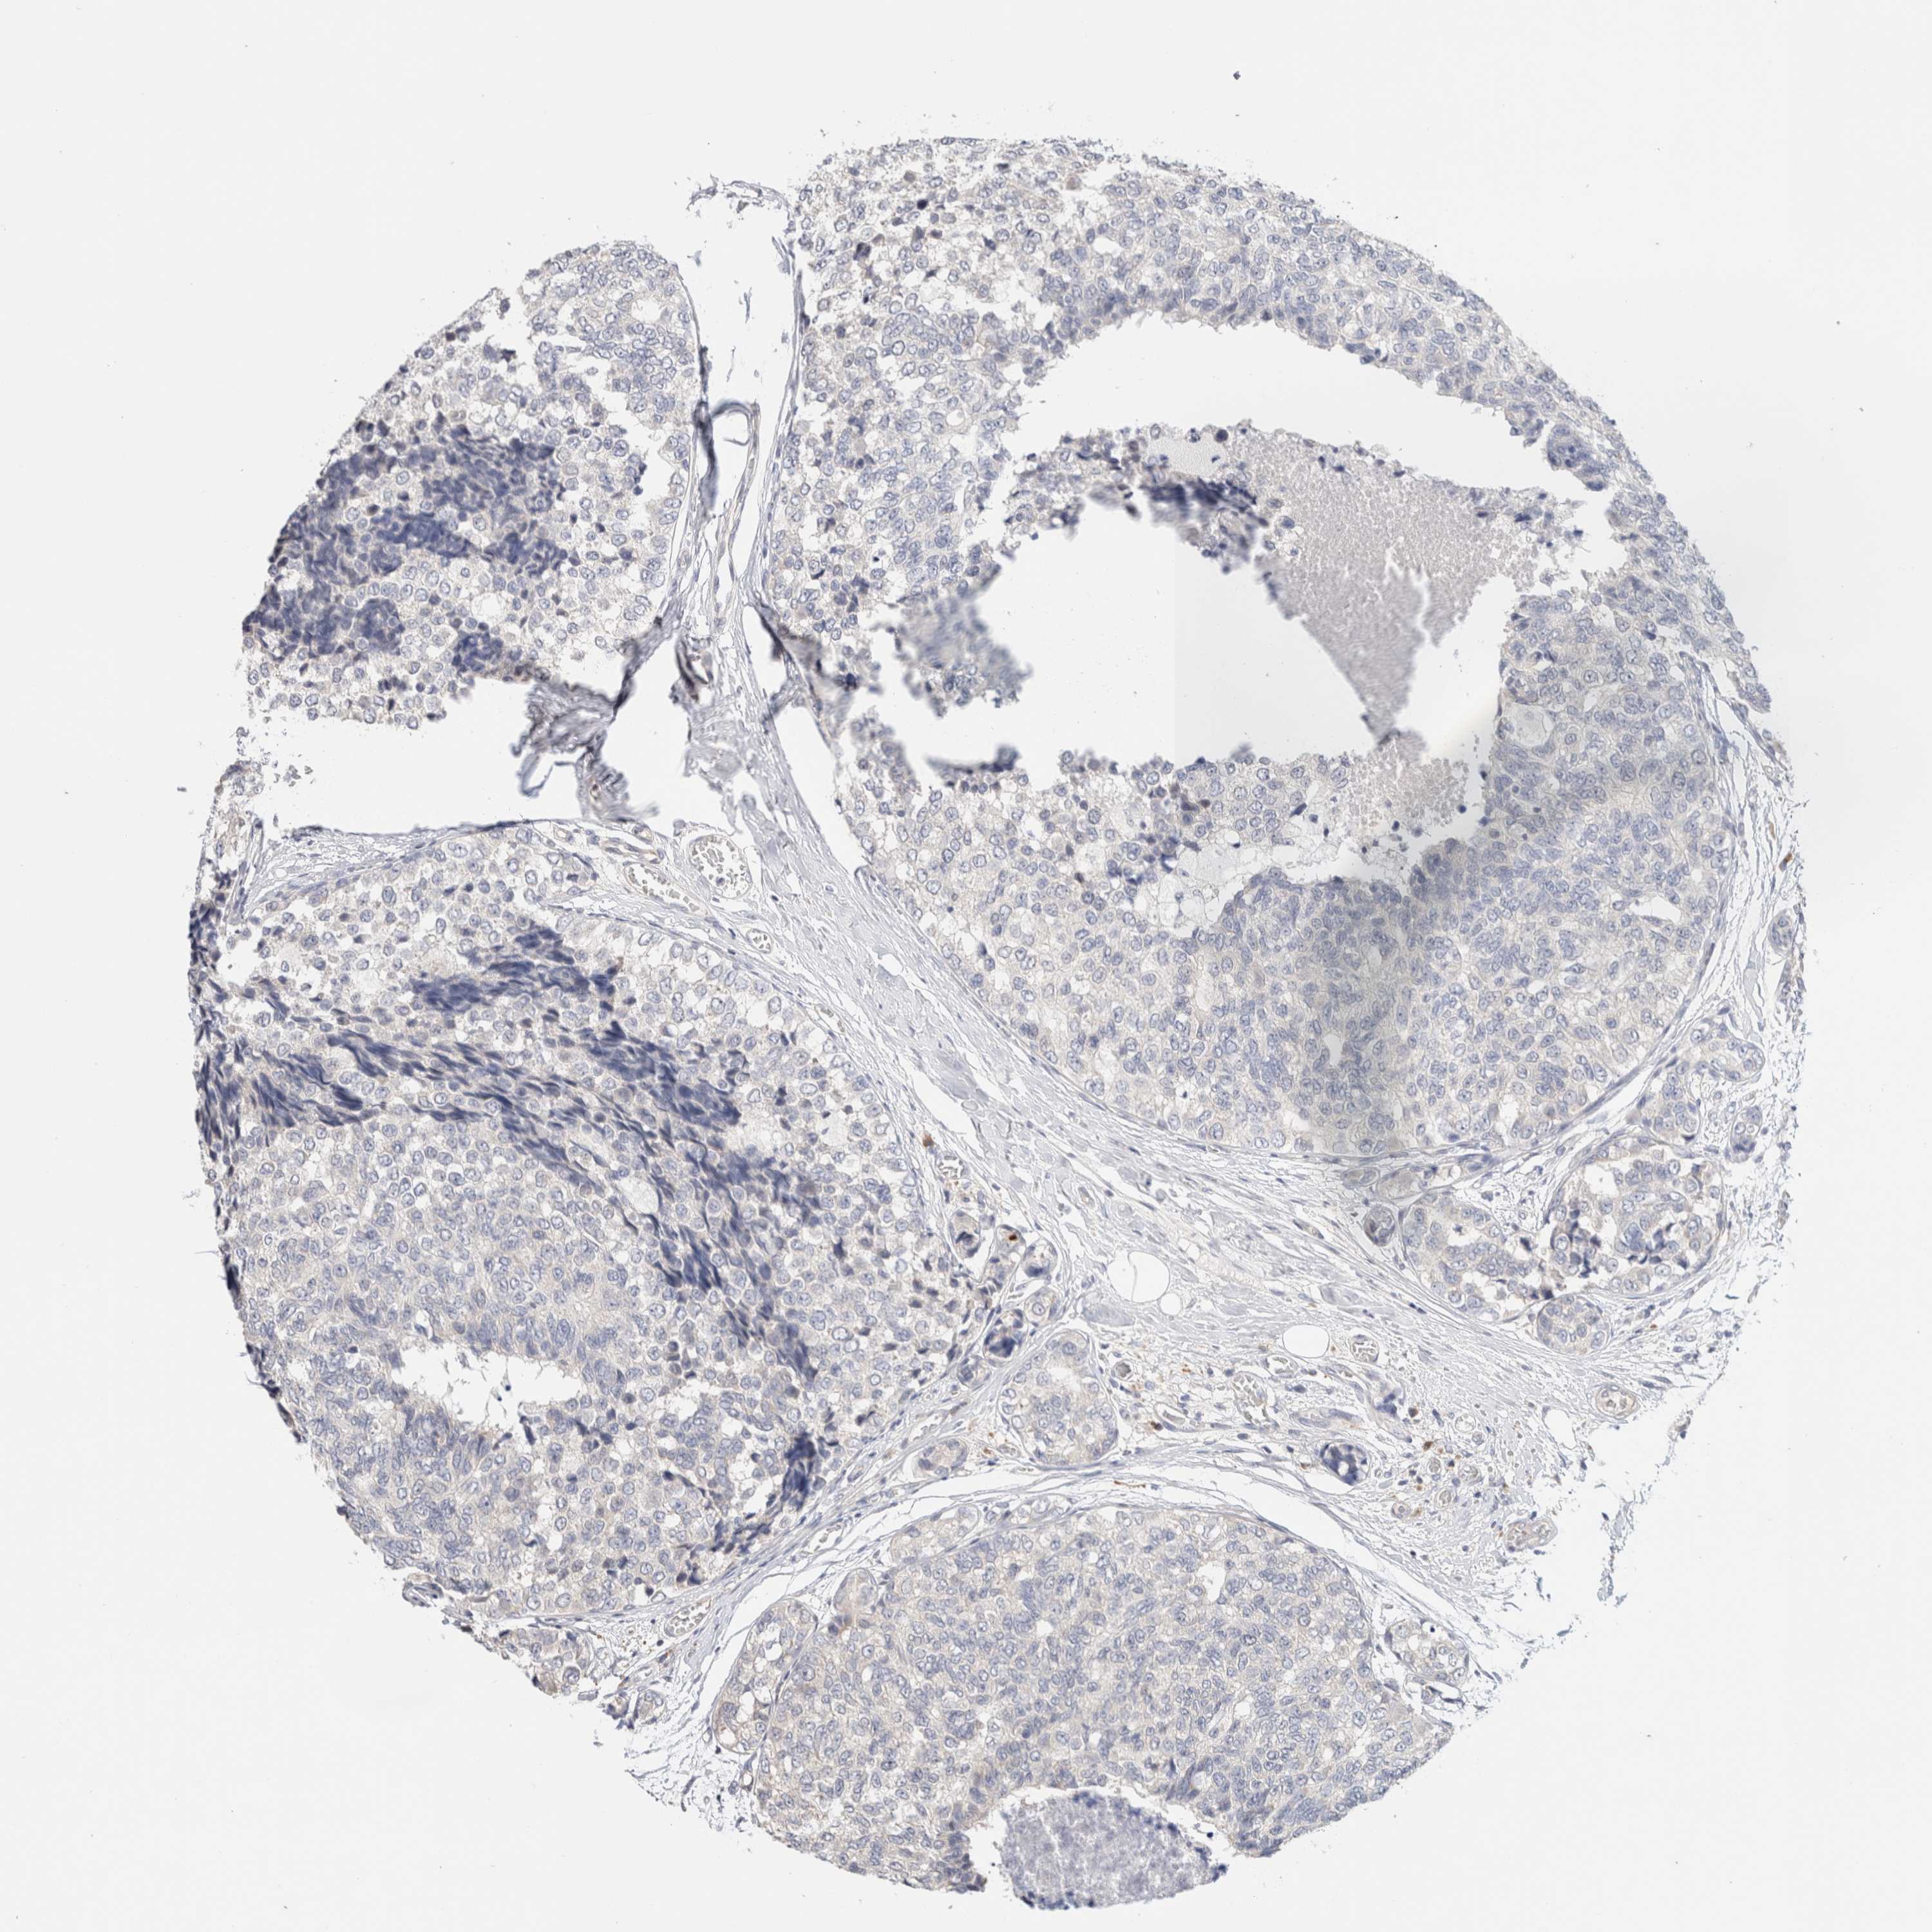

CANCER BREAST CANCER Show tissue menu

BRCA TCGA BRCA VALIDATION PROTEIN EXPRESSION

Breast cancer

Human cancer